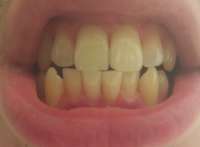

Как и обещал. Забавно, в зеркале кажется не так криво.

Боль на третий день похожа на второй день, спасаюсь болеутоляющим. Но целом уже привык.

Вчера делал панорамный снимок. Всё как >>513480 сказал, ортодонт взял его только посмотреть. Внимание, вопрос знатокам, ортодонт посмотрел на второй пикрелейтед и сказал, что зуб в котором штифт нужно переделывать - канал не полностью залечили, а так же второй зуб - там тоже проблема с каналом и что если ставить брекеты, то им обоим придет пизда. Когда это лечить не понятно, времени в обрез, завтра пойду к своему врачу который год-полтора назад мне эти зубы лечил, послушаю что скажет. В то, что она плохо сделала не хочется верить, но нужно быть реалистом.

>Забавно, в зеркале кажется не так криво.

Я тоже когда фоткаю свою пасть, тот еще адок получается на фото. Не завидую своим собеседникам, если мои зубы и правда так выглядят.